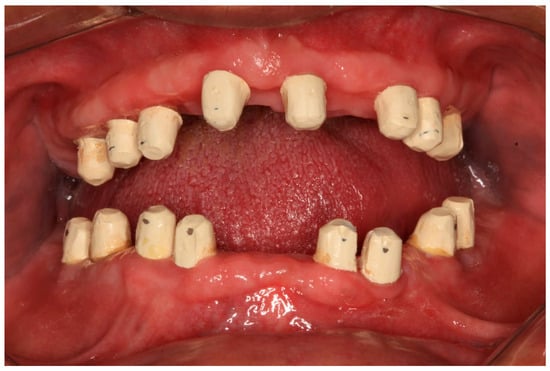

The clinical dental assessment, at the time, indicated a completely edentulous maxilla and a partially edentulous mandible. The residual mandibular teeth exhibited periodontal compromise, classified as Grade 3 mobility according to the Miller Classification, with multiple cavities and a poor overall prognosis (Figure 1).

The suggested treatment plan was to clear the compromised remaining mandibular teeth and to perform full-mouth rehabilitation using cement-retained fixed bridges over zirconia implants. According to the manufacturer’s guidelines, the number of abutments in a cement-retained bridge over zirconia implants should not exceed one pontic. To follow the recommendations, the plan was to do four bridges over eight implants in the maxilla and three bridges over eight implants in the mandible. The treatment plan was discussed with and approved by the patient, who signed a consent form. The treatment started with the extraction of the remaining lower teeth (Figure 2).

Figure 1. Preoperative oral condition. (A) The edentulous maxilla. (B) Partially edentulous mandible. (C) Maxillary denture and mandibular partial denture.